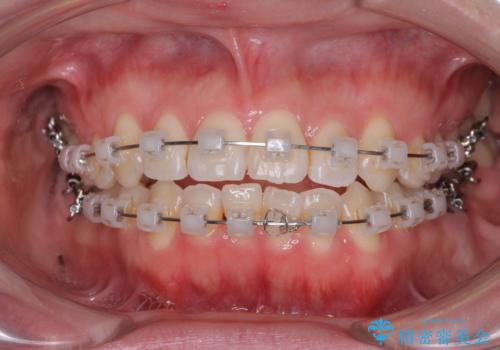

前歯のデコボコを治したい ワイヤー矯正

- クリアブラケット

- 前歯のデコボコが気になるとのことで来院された患者様です。

目立たない装置と金属のワイヤーで矯正治療を行うこととしました。

1年半程度の期間を見込んでいましたが、上下の真ん中の位置をできる限り合わせるための調整に少し時間がかかってしまいました。

咬み合わせが安定し、前歯の汚れも付きにくくなりました。